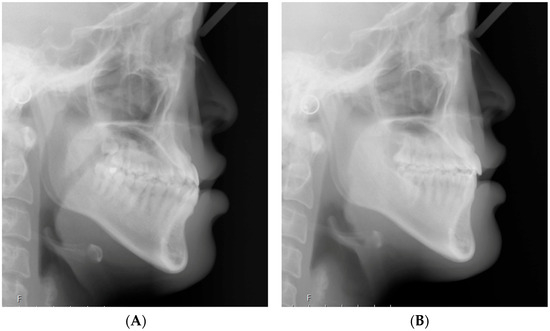

2.2. Cephalometric Analysis

| 6C to VFH (mm) | 21.74 ± 3.88 | 18.09 ± 4.19 | −3.65 | 0.000 * |

| 6R to VFH (mm) | 19.45 ± 4.05 | 17.64 ± 3.94 | −1.81 | 0.000 * |

| 1C to VFH (mm) | 54.68 ± 2.81 | 51.36 ± 2.91 | −3.32 | 0.000 * |

| 1R to VFH (mm) | 47.62 ± 3.50 | 46.81 ± 3.68 | −0.81 | 0.002 * |

| L1-MP angle (°) | 83.88 ± 4.93 | 75.86 ± 4.65 | −8.02 | 0.000 * |

| L6-MP angle (°) | 72.37 ± 8.03 | 66.01 ± 7.74 | −6.36 | 0.000 * |

| Overjet (mm) | 0.19 ± 1.87 | 3.67 ± 0.96 | 3.48 | 0.000 *† |

| Overbite (mm) | 0.68 ± 1.33 | 2.25 ± 0.91 | 1.57 | 0.000 *† |